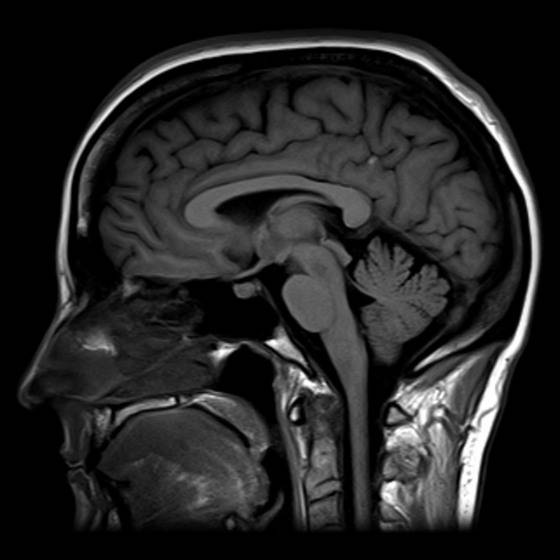

사람 뇌를 자기공명영상(MRI) 장치로 스캔한 그림. [위키피디아]